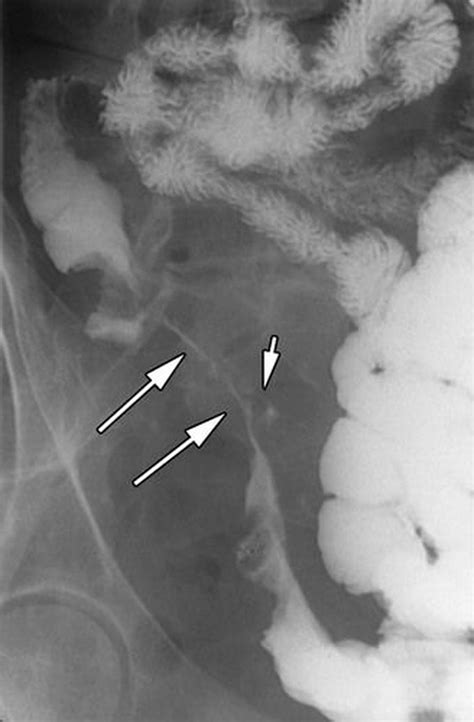

Long segment of narrowed terminal ileum in a 'string like' configuration in keeping with a long stricture segment. For those patients too ill to undergo colonoscopy or ct scan, nuclear imaging may reveal sites of inflammation. 1,2 this sign is not always pathognomonic for crohn’s disease, and the differential diagnosis includes tuberculosis and carcinoma. A thin stripe of flow is caused by decreased pressure and flow distal to the stenosis, which causes a collapse of the distal ica. Tubular narrowing due to spasm or stricture depending on the chronicity. The classic string sign due to stricture formation or spasm is often seen. Web crohn disease of the terminal ileum with ct and sonographic correlation. Contrast radiography and computed tomography scans play important roles in the diagnosis and management of crohn's disease.1many radiographic signs, including cobblestone sign, string sign, and shell sign, are pathognomonic for crohn's disease. Air enteroclysis, mdct, endoscopy, and pathology alberto i.carbo, thretareddy, thomasgates, telcianevesa, jaiyeolathomas, enriquegonzalez On control films presence of gallstones, renal oxalate stones, and sacroiliac joint or lumbosacral spine changes should be sought.

On control films presence of gallstones, renal oxalate stones, and sacroiliac joint or lumbosacral spine changes should be sought. It may be seen in crohn's disease , hypertrophic pyloric stenosis , carcinoid tumor and colon cancer. Long segment of narrowed terminal ileum in a 'string like' configuration in keeping with a long stricture segment. For those patients too ill to undergo colonoscopy or ct scan, nuclear imaging may reveal sites of inflammation. Web the gastrointestinal string sign represents a severe narrowing of loop of bowel, in which a thin stripe of contrast within the lumen looks like a string. Tubular narrowing due to spasm or stricture depending on the chronicity. A thin stripe of flow is caused by decreased pressure and flow distal to the stenosis, which causes a collapse of the distal ica. Air enteroclysis, mdct, endoscopy, and pathology alberto i.carbo, thretareddy, thomasgates, telcianevesa, jaiyeolathomas, enriquegonzalez Web crohn disease of the terminal ileum with ct and sonographic correlation. Termed the string sign of kantour ( gastrointestinal string sign ). Contrast radiography and computed tomography scans play important roles in the diagnosis and management of crohn's disease.1many radiographic signs, including cobblestone sign, string sign, and shell sign, are pathognomonic for crohn's disease.